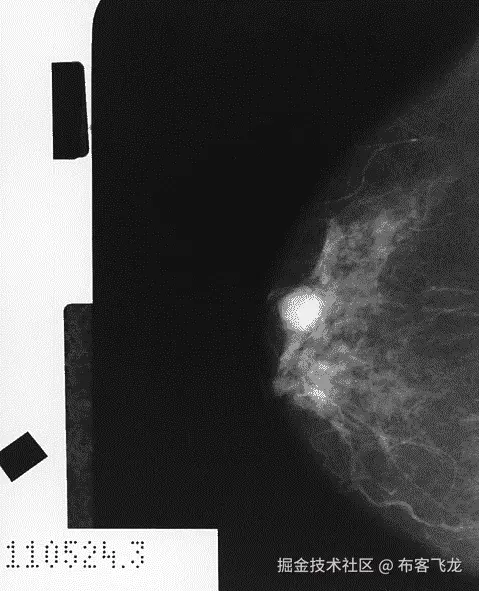

虽然在具有特定症状、风险因素、心电图表现和实验室结果的患者中,CHF 是可能的,但最终诊断只能通过超声心动图或心脏 MRI 来确立。超声心动图需要专业人员来进行测试,然后由专科医生(通常是心脏病专家或放射科医生)来解读结果,并评估心脏的泵血功能。这通常是通过估算射血分数EF)来完成的,射血分数是指左心室在收缩过程中排出血液的比例。65%的 EF 被认为是正常的,40%表示心力衰竭,10-15%则见于 CHF 的晚期阶段。下图取自超声心动图,展示了心脏的四个腔室。你可以想象,使用声波产生的模糊图像来量化心脏功能可能是不可靠的:

心脏 MRI 虽然更昂贵,但在测量 EF 方面更为准确,并被视为 CHF 诊断的金标准;然而,它需要心脏病专家花费最多 20 分钟来解读单个扫描。在下图中,我们看到:

影像学检查是乳腺癌筛查中的下一种最低侵入性测试。用于乳腺癌筛查的影像学方式包括乳腺 X 光检查、MRI 和超声波。2016 年,美国预防服务工作组USPSTF)建议 50 岁及以上女性每两年做一次乳腺 X 光检查(见下图,图示为乳腺 X 光检查,显示出一个被诊断为胶样癌的白色区域;美国国家癌症研究所,1990 年),因为该年龄段的乳腺 X 光检查具有较高的敏感性(77%至 95%)和特异性(94%至 97%),并且它们对患者的潜在危害较低(美国预防服务工作组,2016 年)。